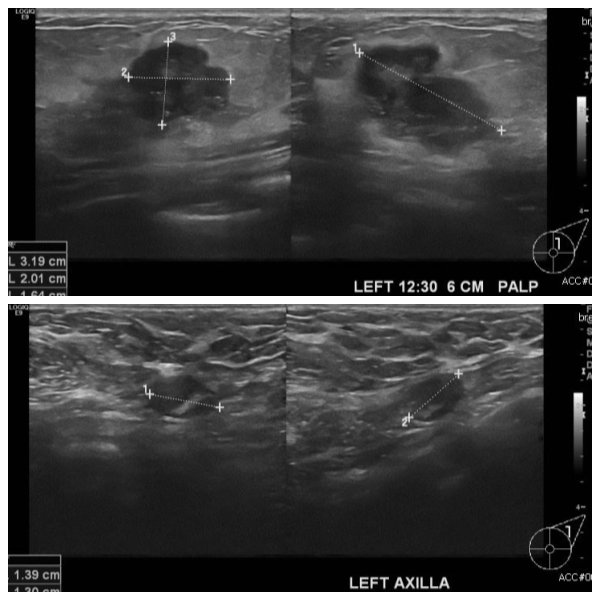

건강검진상 이상 소견으로 내원하신 40대 여성분으로  좌측 유방 12시 30분 방향에

서 6cm 떨어진 거리의 만져지는 혹 중앙핵생검 시행하여 좌측 침윤성 유관암 진단

되었고, 좌측 겨드랑이에 림프절 비대 세침검사 시행하여 전이암 진단 되었습니다.